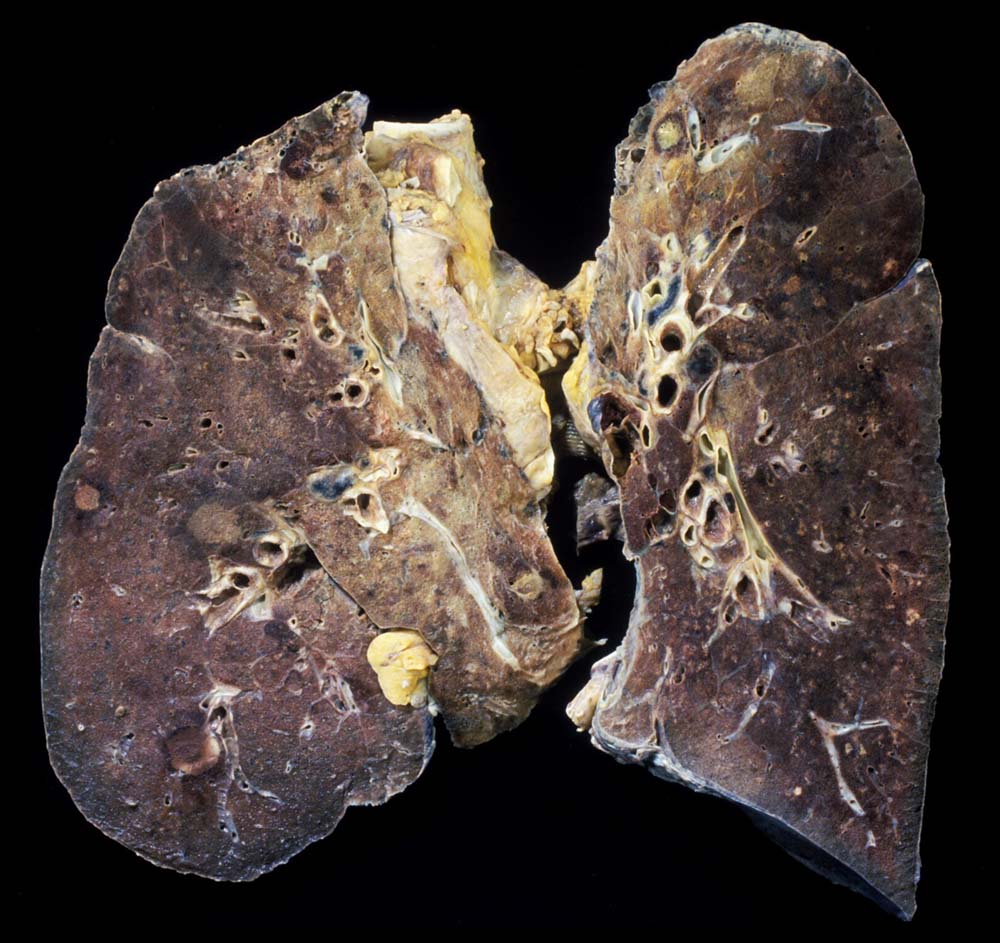

PathoPic – image database / PathoPic ID 9032 - Invasive pulmonale Aspergillose: anämische Lungeninfarkte

Invasive pulmonale Aspergillose: anämische Lungeninfarkte

Lunge

Akute invasive pulmonale Aspergillose, sämtliche Lungenlappen betreffend.

Diffuser Alveolarwandschaden. Pilzsepsis mit weiteren Herden im Gastrointestinaltrakt.

Makroskopie